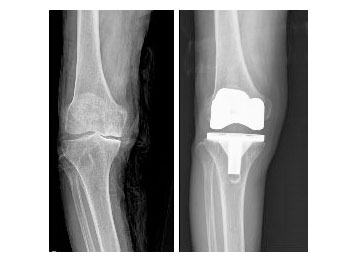

• 퇴행성관절염으로 인공관절치환술 사진

퇴행성관절염으로 인공관절치환술 시행